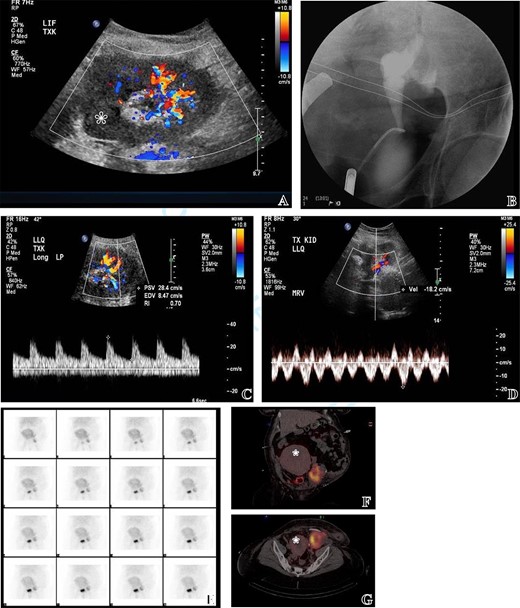

The urology and transplant teams assessed the injury. The injury to the kidney allograft extended through the upper third of the parenchyma and skived toward the hilum violating the upper polar vessels and calyx (Fig. 2). After bleeding control, assessment of the remaining part of the allograft was performed using intraoperative doppler ultrasound and cystourethrogram (Fig. 3). Doppler ultrasound revealed that most of remnant allograft had an intact arterial signal with exception of a geographical area proximal to the cut edge equivalent—roughly—to 20–30% of the remaining allograft. The venous signal was intact with no concerns (Figs. 2 and 3). The cystoscopy and retrograde pyelography revealed an intact lower calyx. The upper calyx was violated but not vital to the urinary drainage of the remnant allograft. The remnant part of the allograft constituted roughly 65% of the total allograft size. Thus, the decision was made to proceed with a salvage attempt.

(A) Intraoperative US doppler at the cut surface of the allograft revealing partial perfusion of the allograft as some areas lacked vascular signal reflecting poor perfusion (labelled with asterixis). (B) Intraoperative retrograde ureterogram to test for urine

leaks after closure of the upper calyx. (C, D) Post-operative US evaluation revealing preserved arterial and venous signals in the perfused parts of the allograft. (E, F, G) Post-operative diagnostic MAG3 scan documenting preserved perfusion and function of the allograft with no evidence of leak. The images demonstrate the proximity of the allograft to the gravid uterus (uterus labelled with asterixis).